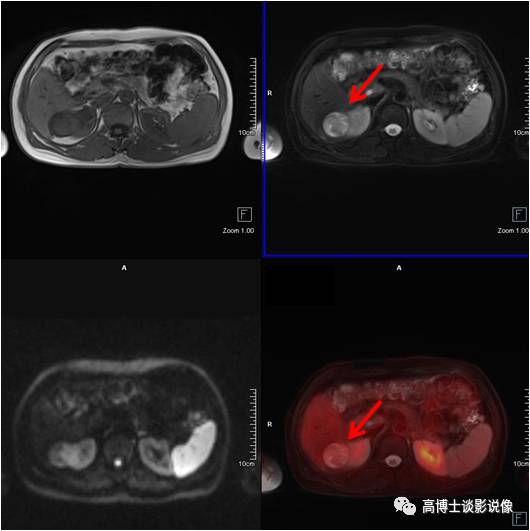

淋巴管瘤

中年男性,肝转移瘤患者。脾脏可见1枚异常信号灶,大小约2.8cm×3.6cm,FDG无代谢,考虑为良性病变,脾脏淋巴管瘤。

点评

脾脏淋巴管瘤也属于脾脏良性肿瘤,系由囊性扩张的淋巴管构成,生长缓慢,病灶小,无临床症状者,不需要外科处理,B超定期复查。此例病灶FDG无代谢,PET/MR帮助排除脾脏转移。